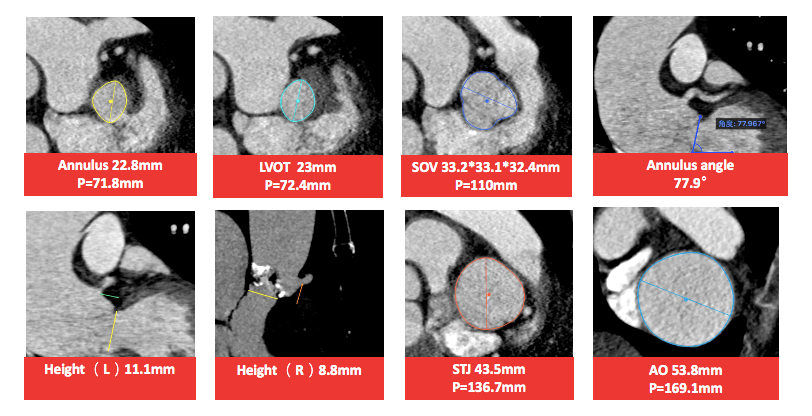

主动脉CT

主动脉根部形态,横位心明显

瓣环:周长71.8mm, 平均直径22.8mm, 左室流出道平均直径23.0mm;

瓣上:瓣上4/6/8mm, 预估瓣膜展开空间平均直径22.2/24.6/27.7mm;

冠脉:左右冠脉高度分别11.1mm/8.8mm,需注意冠脉风险;

角度:释放角度CAU 6 LAO 10;

入路:左右股动脉均在7mm以上,推荐右股动脉为主,

推荐:植入VitaFlow Liberty™ 27mm瓣膜

备注:极度横位心,建议结合抓捕器使用;降主动脉与腹主动脉严重扭曲,

升主动脉扩张,且无窦管结合部,仅有瓣环和左室流出道可以起到锚定作用。